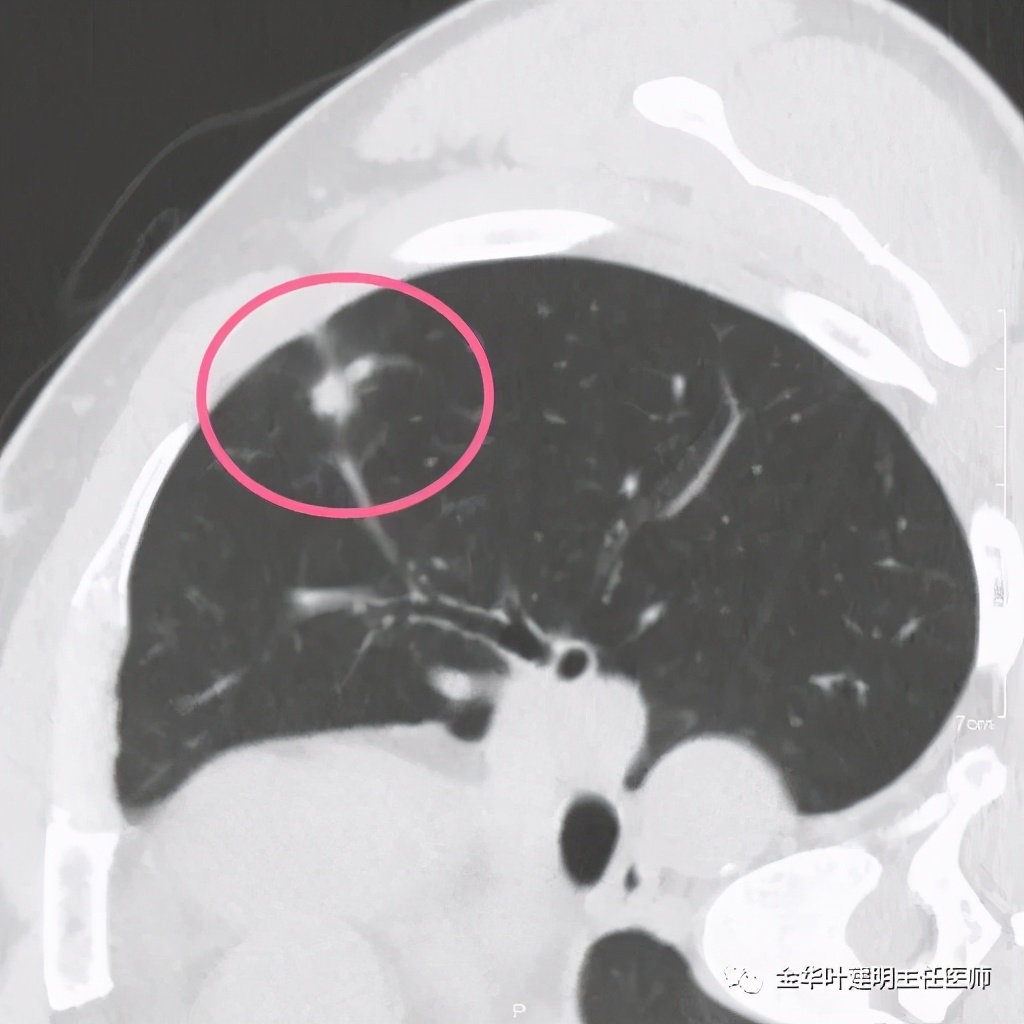

患者为48岁男性,检查发现左肺上叶实性结节,临床没有炎症表现,肿瘤指标不高,没有查过结核及隐球菌荚膜抗原试验或G试验、M试验等。我们先来看其前一个月时的平扫影像:

上图示有血管征,与病灶关系较密切

上图示血管与病灶临近,但没有被病灶牵拉从而进入病灶

我们见左上实性病灶,主病灶旁有卫星灶,有血管进入,但也有贴边走行,边缘略显模糊,膨胀感与细毛刺不明显,收缩力也不明显。下面是其靶扫描的片子: